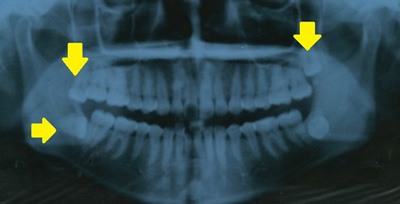

市川市二十歳の歯科健康診査ではパノラマ・レントゲン写真で親知らずの状態やリスクの有無などをみます

パノラマ・レントゲン撮影の結果、親知らずのある人は80.9%

パノラマ・レントゲン写真に写っている親知らず

黄色い矢印の先